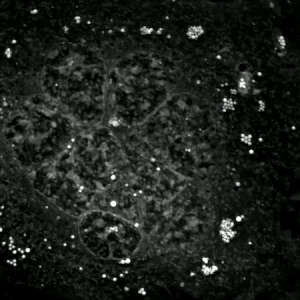

An etoposide-treated DU145 prostate cancer cell exploding into a cascade of apoptotic bodies. The sub images were extracted from a 61-hour time-lapse microscopy video, created using quantitative phase-contrast microscopy. The optical thickness is color-coded. With increasing thickness, color changes from gray to yellow, red, purple and finally black. See the video at The Cell: An Image Library | |